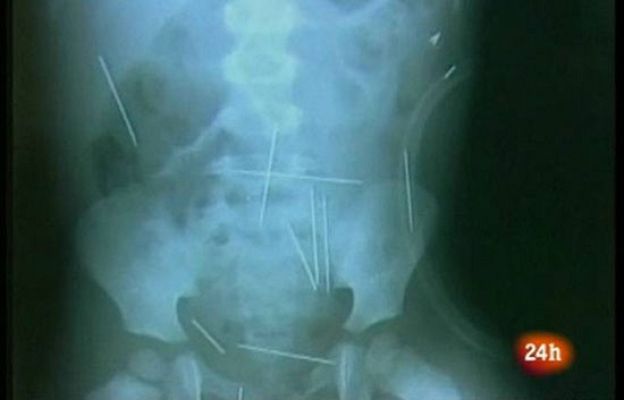

El brasileño Roberto Carlos Magalhães ha confesado haber aplicado 40 agujas a su hijastro, de dos años de edad, que está ingresado en estado grave en un hospital del estado de Bahía. El padrastro ha asegurado que llevó al niño varias veces a casa de una mujer llamada Angelina, donde clavó las 40 agujas con su colaboración y la de una tercera persona, cuyo nombre no ha sido divulgado. En su declaración, ha explicado que lo hizo a petición de Angelina, a quien le hizo caso porque estaba interesado sexualmente en ella. El niño permanece ingresado en un hospital y espera al inicio de la operación en la que se le van a extraer las agujas, que incluso le han perforado un pulmón. (17/12/09).